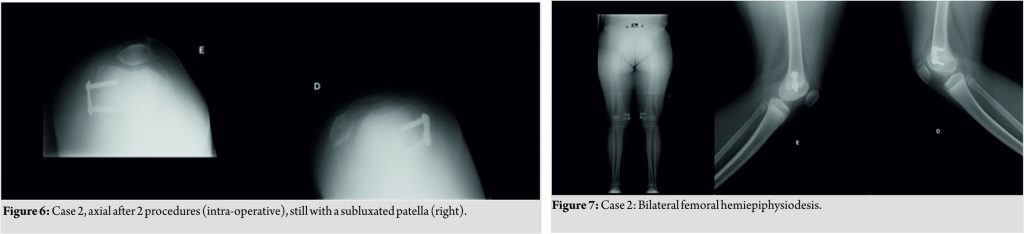

The second child presented with a complaint of recurrent falls, bilateral valgus, bilateral significant femoral anteversion, and the two Dugdale V knees (Fig. 5). At 6 years of age, he was submitted to surgery in the right knee (2010) and in 2011 in the left. As in the right knee he still had subluxation of the patella, we performed in the left knee, an associated and modified Galeazzi procedure reconstructing the medial patellotibial ligament, leaving the semitendinosus inserted in the tibia, and setting the reconstruction with osseous points on the patella medially. After 3years, as valgus of the right knee increased and continued with dislocation in flexion, we performed bilateral medial femoral hemiepiphysiodesis procedure (Fig. 6 and 7).